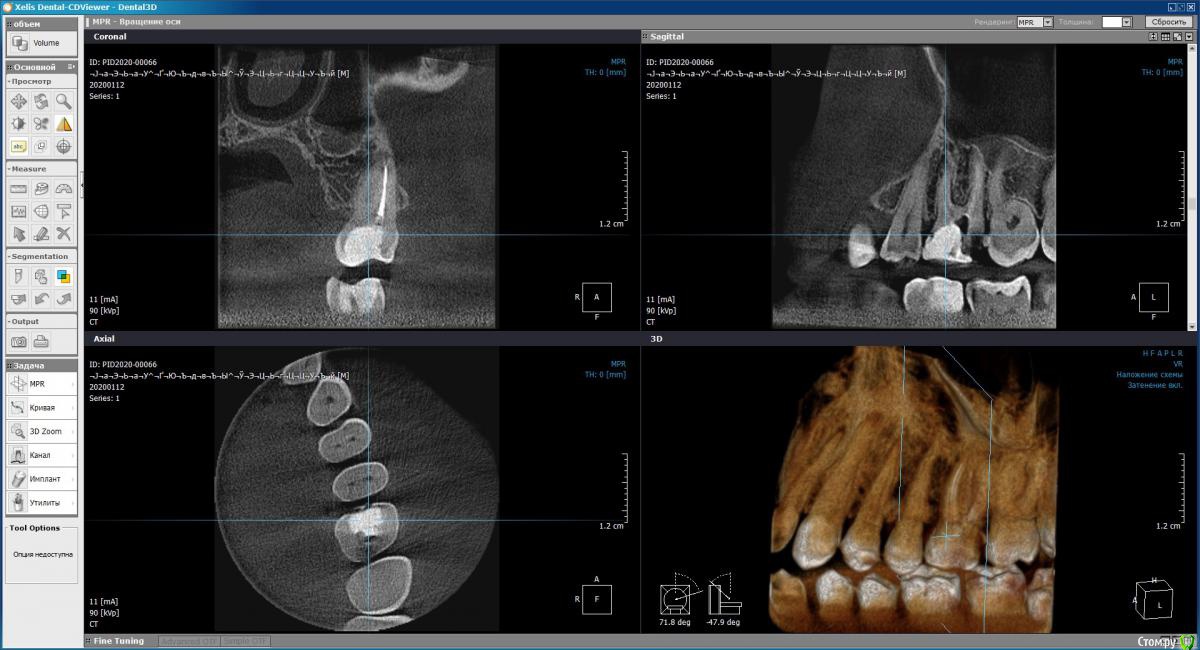

Demon_L Опубликовано 23 января, 2020 Поделиться Опубликовано 23 января, 2020 (изменено) Мне 36 лет, примерно 12 лет назад залечивал зуб (верхняя левая 6-ка), запломбировали 3 канала гуттаперчей, поставили обширную световую пломбу в хорошей платной клинике.Позже я стал замечать, что зуб немного темнее остальных, но не придавал этому значения, т.к. зуб не беспокоил. На днях откололся небольшой кусочек от этого зуба, пошел в клинику, сделали снимок КТ, сняли пломбу. Вердикт - 3 канала не требуют перелечивания, но есть 4-й канал, который требует лечения и который не нашли первый раз. Но что самое печальное - обнаружили перфорацию дна полости, которую по ошибке сделали при первом лечении, видимо когда искали 4-й канал. Тогда же видимо и положили раствор резорцин-формалина, что и придало темный с отттенками красного цвет зубу.Пока не нашли перфорацию, по снимкам склонялись к установке коронки, но после того, как обнаружили, один врач настойчиво рекомендовал удаление и имплантат, другой допускает коронку, но тоже рекомендует имплантат.Хотел бы спросить Вашего мнения, действительно ли при наличии перфорации дна полости (она небольшая, но файл в неё проходит и выступает капелька крови) ставить коронку противопоказано?Можно ли сначала залечить перфорацию, а потом ставить коронку? Прибегать к удалению и имплантации хотелось бы в последнюю очередь.Прилагаю несколько снимков КТ. Если они недостаточно информативны, готов выложить с любого другого ракурса. Могу вообще поделиться isо-файлом со снимком (образ CD), тогда можно будет покрутить в 3D как угодно у себя на ПК (запускается автоматически без установки чего-либо).Заранее спасибо за консультацию. Изменено 23 января, 2020 пользователем Demon_L Ссылка на комментарий

Дмитрий Л. Опубликовано 29 января, 2020 Поделиться Опубликовано 29 января, 2020 (изменено) Не соглашусь категорично. По кт там даже четвертый канал искать не надо. У вас 12 лет пролеченный зуб без проблем стоит. Темный цвет и скол решается коронкой.Риск трещины зуба есть. Этого зуба и любых других. Все удалить?Непонятно зачем перфорацию заново раскрыли. Идите в другую клинику, просите закрыть перфорацию и ставьте новую пломбу. Или коронку*Это вывод из ваших слов и приложенных срезов. Изменено 29 января, 2020 пользователем Дмитрий Л. Ссылка на комментарий